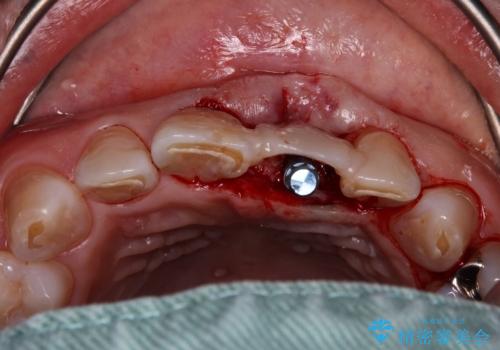

歯肉形態を概ね回復するタイミングでインプラントを埋入し、補綴治療を行うこととしました。

歯肉移植術による更なる歯肉ラインの改善も検討しましたが、笑ったときに歯肉ラインは唇に隠れてしまうため、現在の位置にて仕上げることとしました。

骨の前後幅が小さかったため、細いインプラントを選択せざるを得ない状況でした。咬合力が非常に強い方のため、就寝時のマウスピース装着を徹底していただき、インプラントへの負担を軽減することとしています。